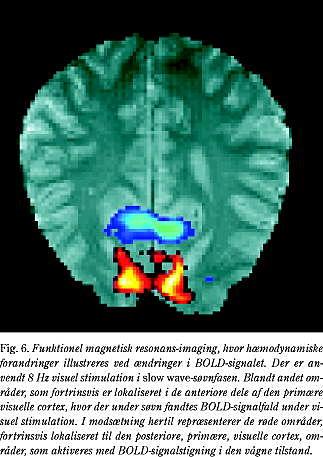

Stimulation under søvn

Det er muligt, om end vanskeligt, at få forsøgspersoner til at sove i en scanner og endog at stimulere dem noget af tiden, uden at de derved vækkes. Nylige fMRI-undersøgelser af visuel

stimulation under søvn har ført til interessante observationer, idet aktiveringsmønstret er helt forskelligt fra det, der ses hos vågne forsøgspersoner. Den visuelle stimulation blev gennemført med blinkende lys (som kan registreres, når øjnene er lukkede). Hos vågne forsøgspersoner (med lukkede øjne) ser man, som ved andre former for stimulation, en kraftig aktivering med øget BOLD-respons i den visuelle cortex, men hos de sovende forsøgspersoner sås et fald (Fig. 6). Efterfølgende undersøgelser med PET-teknikken har bekræftet, at der rent faktisk er et fald i blodcirkulationen i den visuelle cortex hos de sovende forsøgspersoner i modsætning til en stigning i gennemblødningen hos de vågne forsøgspersoner (personlig meddelelse). Umiddelbart kunne fundet virke noget besynderligt og paradoksalt. Men egentlig svarer det ganske godt til reaktionerne under søvn. Det vides således at være svært at vække en sovende forsøgsperson

med pludselige lysstimuli, hvorimod lydstimuli som fx et vækkeur meget lettere bringer en ud af søvnen. Denne specielle form for deaktivering er også iagttaget i enkelte andre tilfælde, bl.a. hos mindre børn (27).